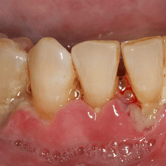

Recesión gingival

La recesión gingival es la pérdida de tejido de las encías que expone la raíz del diente.

Los pacientes suelen observar que sus encías se han retraído y pueden ver las raíces de sus dientes. Esto puede aumentar la sensibilidad dental y el riesgo de caries en las raíces expuestas.

El tratamiento puede incluir injertos de encía y modificaciones en la técnica de cepillado.